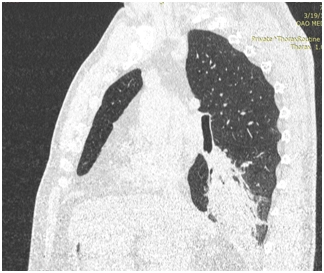

КТ ОГП 06.01.2017. КТ-картина внутрипросветного патологического мягкой плотности компонента (центральный рак?) в промежуточном бронхе правого легкого с ателектазом нижней доли. Лимфаденопатия правого корня, количественная лимфаденопатия средостения.

КТ ОГК от 28.03.2017. По сравнению с предыдущим КТ от 06.01.2017 отмечается выраженная положительная динамика изменений за счет отсутствия образования в просвете промежуточного и нижнедолевого бронхов справа, отсутствия ателектаза нижней доли, а также умеренного уменьшения в количестве и размерах лимфатических узлов средостения и корня правого легкого.